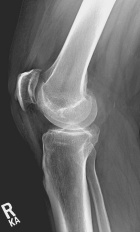

51 year old male with six month history of knee pain, worse after MVC

Zoom image: Radiological image Radiological image.